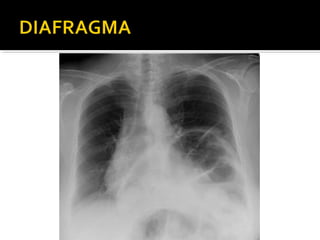

Este documento fornece parâmetros técnicos para realizar uma radiografia de tórax, incluindo posicionamento correto do paciente, dose adequada de radiação e estruturas anatômicas a serem avaliadas, como coração, pulmões, pleura, diafragma e ossos do tórax.